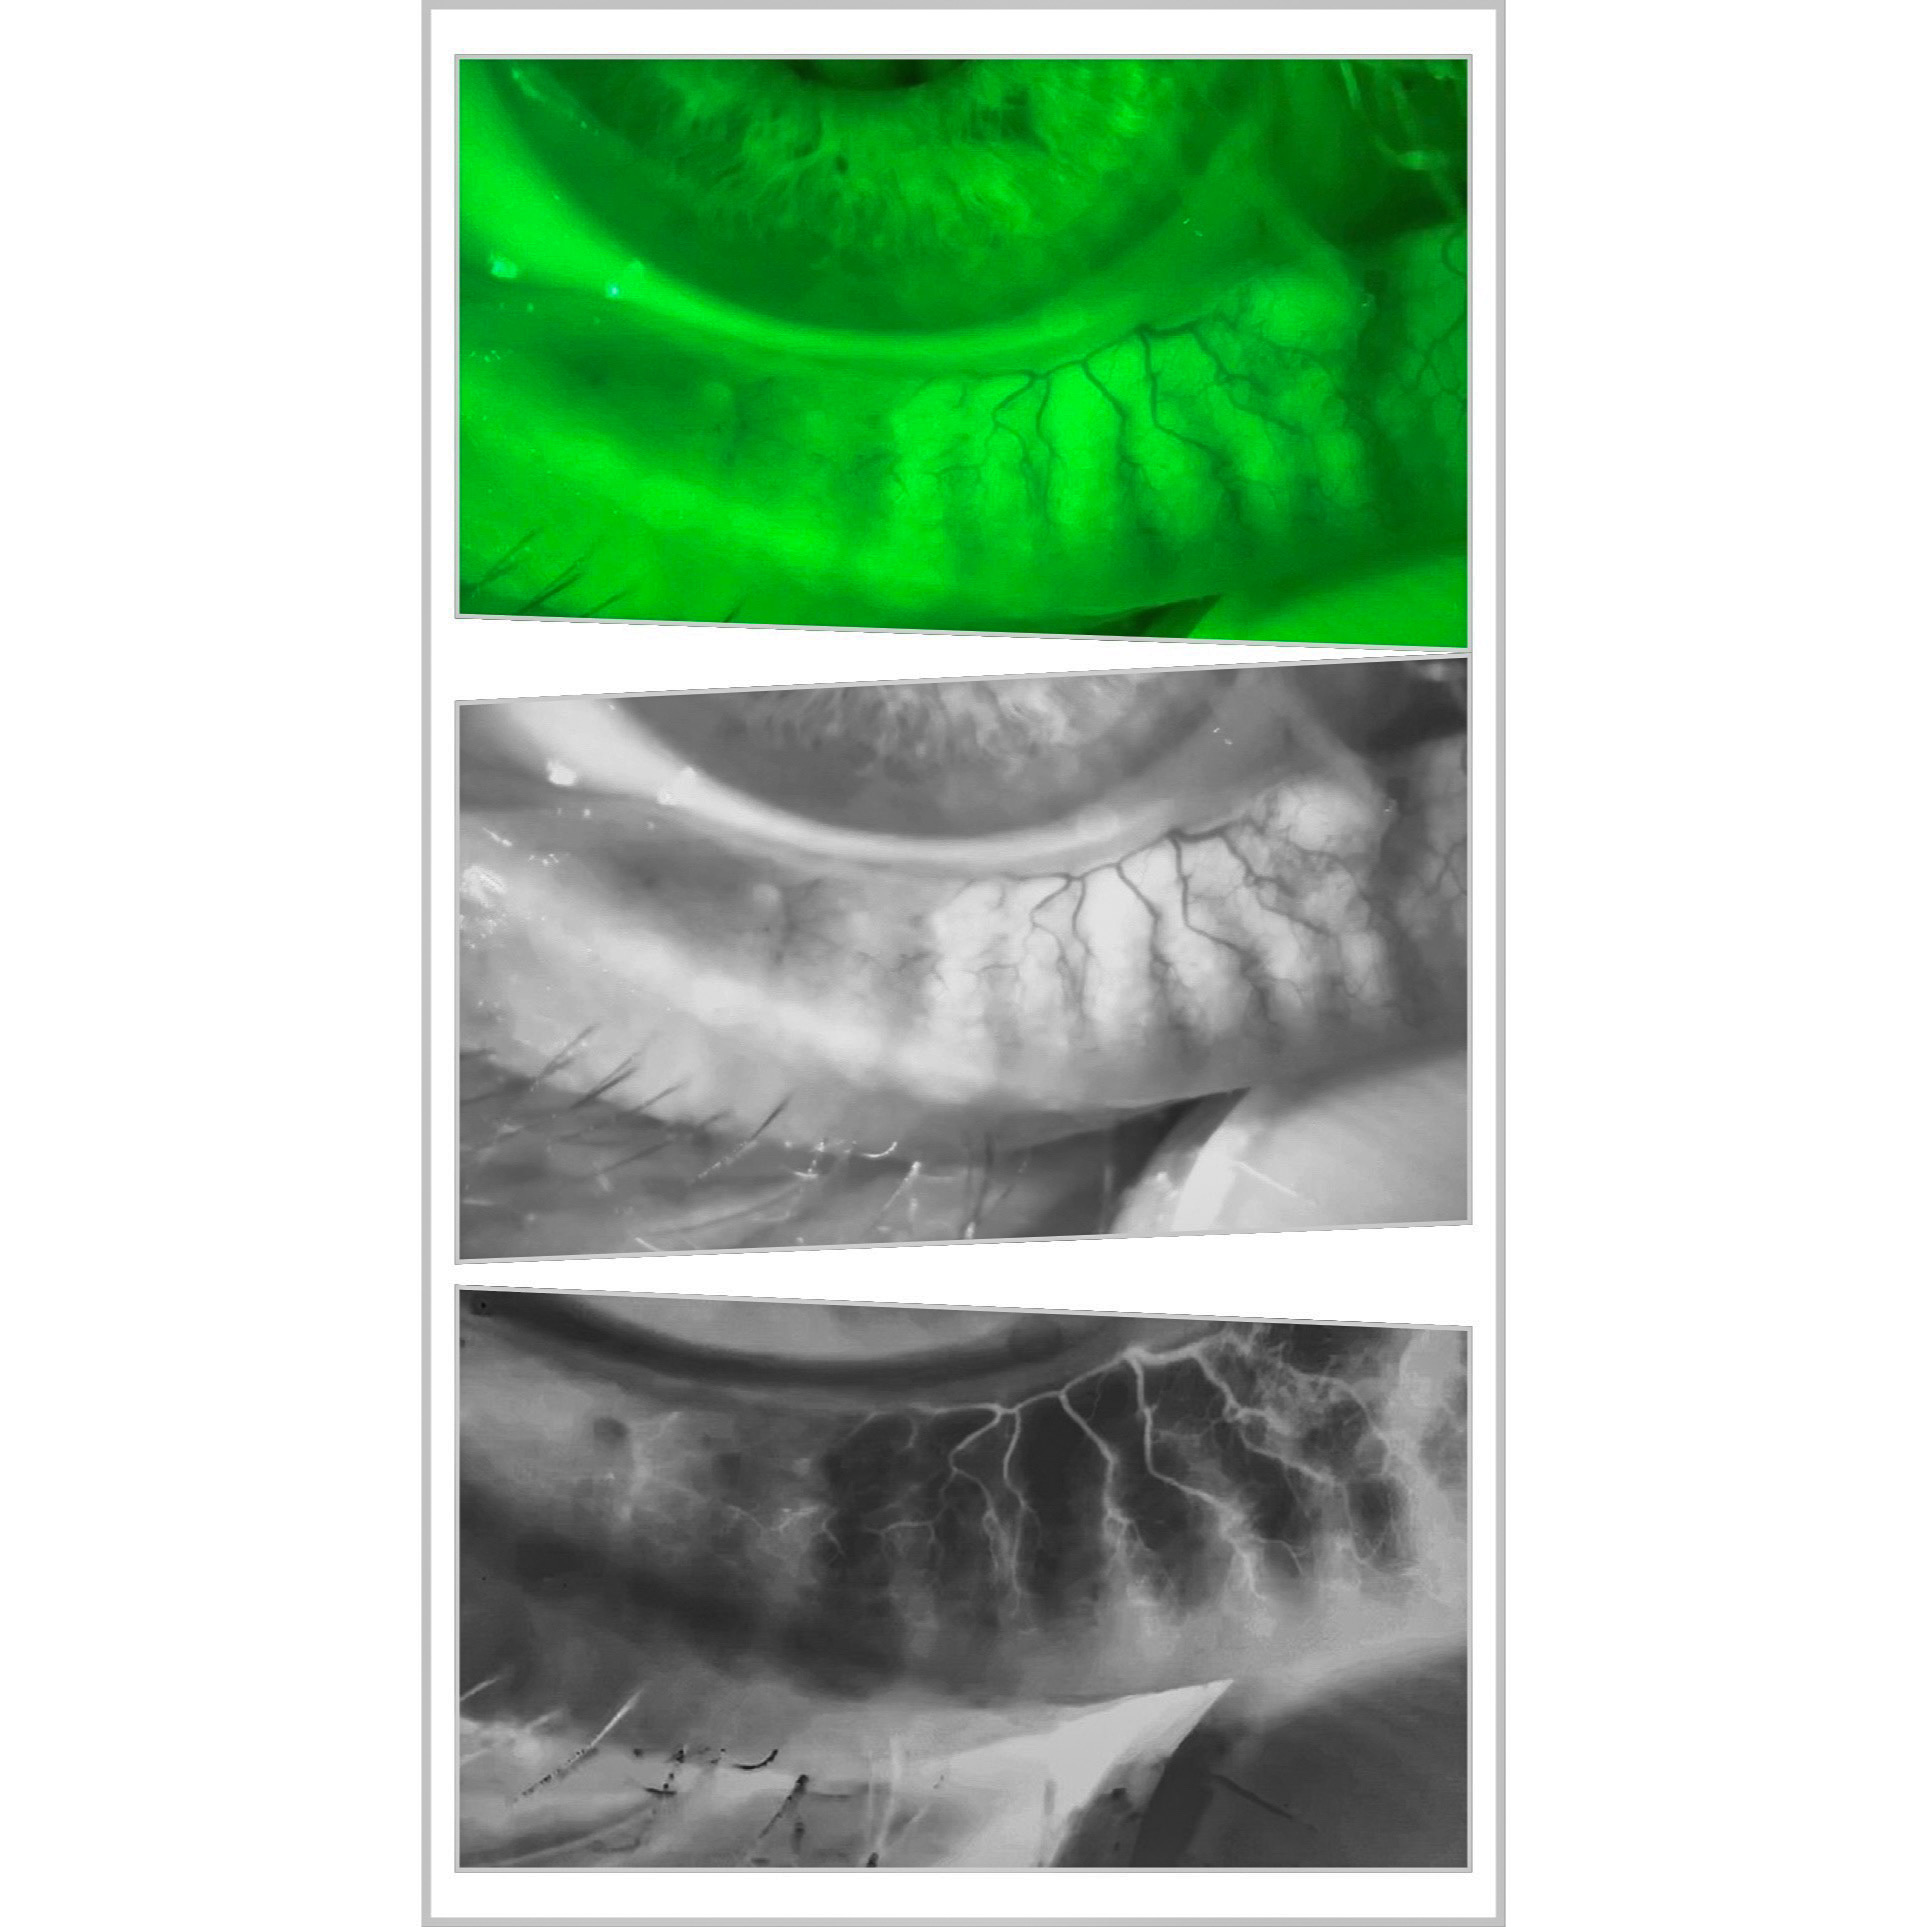

Real Clinical Photos

Actual, unedited images and videos captured with the system.

Color images may be instantly converted to black and white – and then inverted.